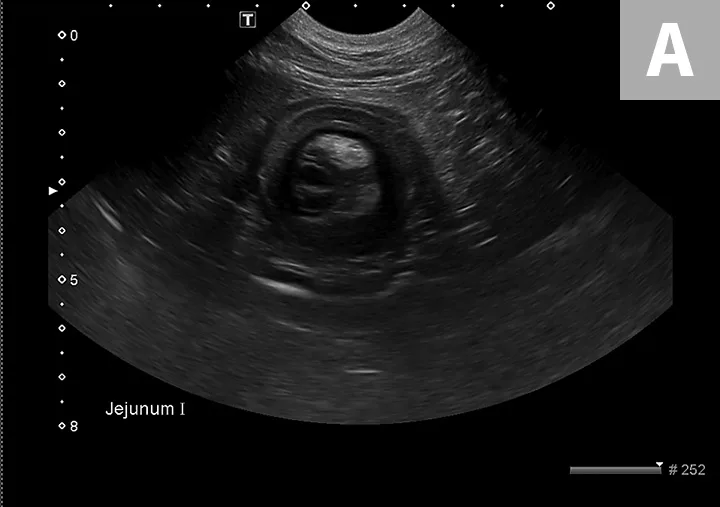

Diagnostic steps include a complete physical examination, abdominal radiography, and abdominal ultrasonography (or a contrast study if ultrasonography equipment is not available). On physical examination, a thickened tubular structure may be palpated in the abdomen, which may be painful for the patient. Abdominal radiographs commonly reveal a fluid- or gas-filled bowel consistent with a mechanical obstruction.2 Abdominal ultrasonography is often the most helpful preoperative diagnostic tool (Figure 1); the finding of multiple hyperechoic and hypoechoic concentric rings in transverse sections, parallel lines in longitudinal sections, or both is diagnostic of intestinal intussusception.4 Abdominal radiography with contrast media (ie, barium) can outline the intussusceptum in the lumen of the intussuscipiens, or the contrast can appear as a ribbon-like structure in the intussusceptum.2

FIGURE 1

Abdominal ultrasound images of a dog with jejuno-jejunal intussusception secondary to an intestinal sarcoma (A), a dog with ileocolic intussusception (B), and a dog with jejuno-jejunal intussusception without an identifiable underlying cause (C)